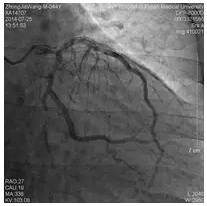

冠脉造影

造影时间:2014年07月25日。

造影结果(一):

造影结果(二):

造影结论及应对策略:本病例行冠脉造影发现: 右冠优势型,LM末端斑块溃疡、LAD、D未见明显狭窄,mLCX约95%狭窄,OM无明显狭窄,TIMI血流3级,见回旋支到右冠侧枝循环。mRCA闭塞。造影后向患者家属交代病情,与家属沟通后决定做介入治疗。